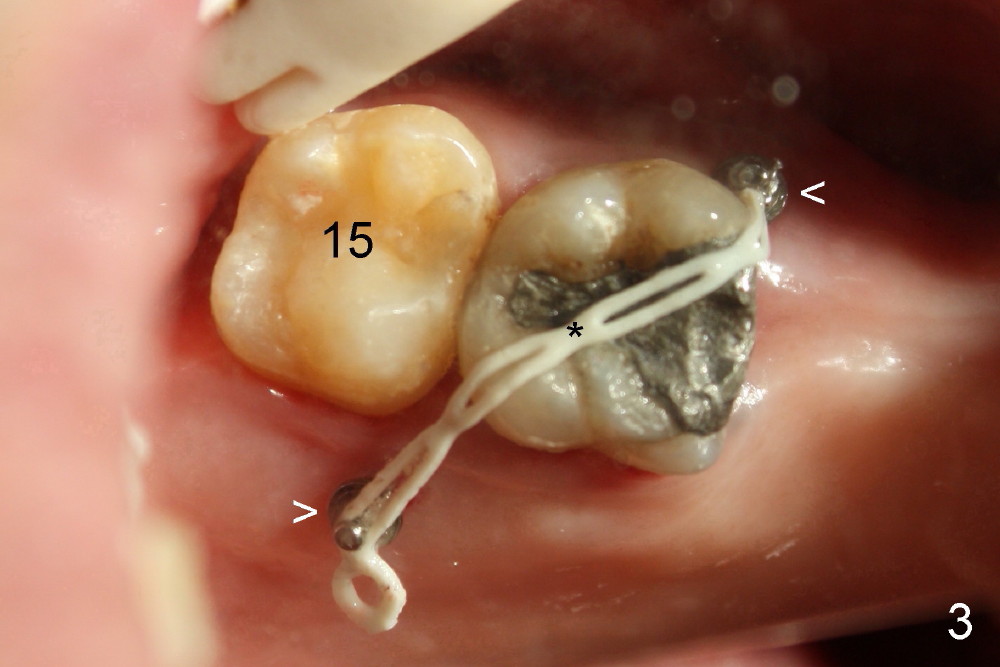

A 51-year-old man needs implants at the sites of #12,13,19 (Fig.1). The teeth #12 and 13 are extracted. An implant is placed at #19 (Fig.2 <). After osteointegration, an abutment is placed (Fig.2 A). The opposing tooth, #14, is found supraerupted. Two mini-implants are placed at the mesiobuccal and distolingual areas of #14 (Fig.3 (mirror view) <) and a power chain (*) is placed for intrusion. In the next 8 months, these 2 mini-implants become loose. Two new mini-implants are placed in the mesiolingual and distobuccal regions (Fig.4 ^). The one in the distobuccal region is loose after a while (Fig.6,7 >). In brief, mini-implants are not efficient in intrusion. At this time, the implants at the sites of #12,13 apparently osteointegrate (3 months post placement) and abutments are placed (Fig.4). Provisional crowns are fabricated (Fig.5). Brackets are placed between #11 and 15 with the bracket at #14 placed more coronally than those of the neighboring teeth (Fig.6-8). Mesially there are two excellent anchorages (#12,13) as well as the mesiolingual mini-implant. The distal anchorage is #15. In the next 5.5 months, the tooth #14 is intruded (Fig.9,10), but the 2nd molar is mobile (not as strong as #14). A longer mini-implant is placed in the distobuccal corner (>, more apical than before (Fig.7)). The distobuccal mini-implant is found to be mobile in 3 weeks (Fig.11). It appears that there is enough clearance for restoration of #19 (Fig.12). Power chains are placed between the mesiolingual mini-implant and #14 buccal tube until the appointment for crown prep. In this way, the lingual cusps may ascend (Fig.13 red arrow), while the buccal ones may descend (black arrow). The occlusal clearance will be more favorable.